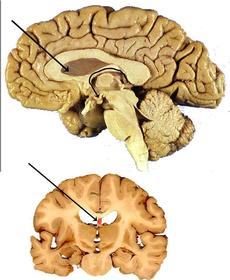

Gray Commissure communication route between R&L sides of gray matter.

White commissure Connects the white matter to the R&L sides of spinal cord.

Anterior median fissure Divides spinal cord into 2 anterior sections

Posterior median sulcus median portion of the spinal nerves enter the spinal cord.

central canal houses the spinal cord and CSF fluid

Septum Pellucidum contains neurons and glial cells.

corpus callosum axons that connect two hemispheres.